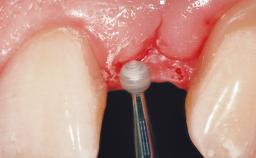

Late Flapless Placement of an Implant in a Maxillary Left Central Incisor Site

A 39-year-old male patient presented with a chief complaint of discomfort and gingival discoloration around his maxillary left central incisor. He was in good general health and was a non-smoker. His past dental history was significant because of the traumatic fracture of tooth 21 in a sporting accident at age 13. Initial dental treatment included endodontic therapy and a full-coverage restoration. The patient became symptomatic 5 years later, when structural failure of the tooth resulted in the dislodgment of the crown. Endodontic retreatment, apical surgery, and post-and-core restoration were performed.